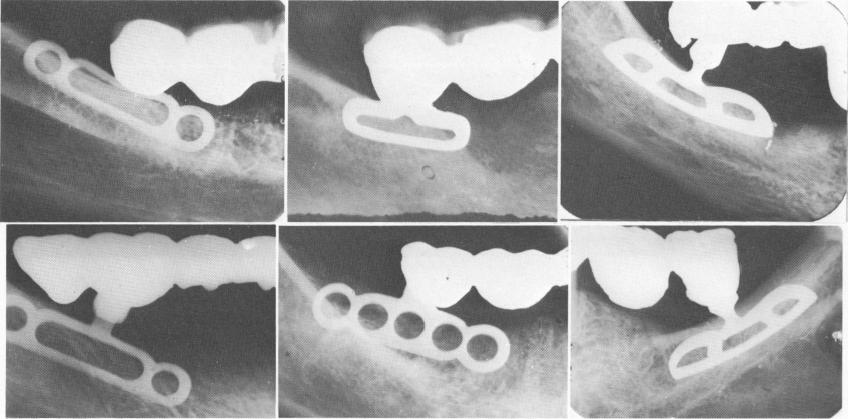

Fig. 11-15. Blades for shallow areas. (From Linkow, L. I.: The endosseous blade, a new dimension in oral implantology, Rev. Trim. Implant., Nov., 1968.)

1 Various dental blades for shallow areas in upper and lower jaws